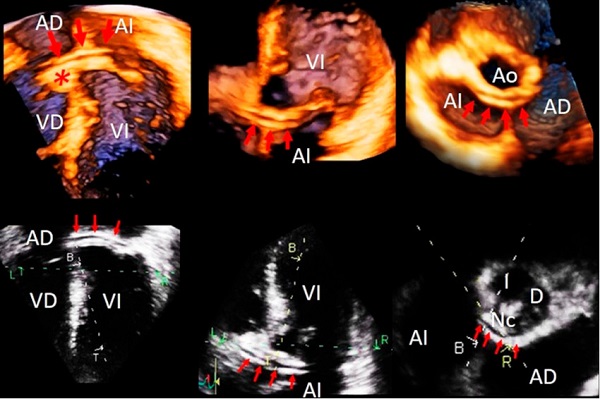

Se adquirió un volumen completo desde la vista apical de 4 cámaras. En el análisis postproceso se pudo seguir el trayecto del vaso (Figura 2, panel superior) y se confirmó en varios planos que se trataba de una arteria coronaria y no de un artificio (Figura 2, panel inferior).